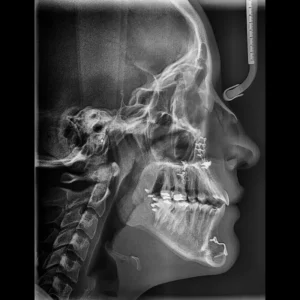

Cirugía ortognática (asimetrías faciales)

Corrección quirúrgica de deformidades óseas en mandíbula y maxilares para mejorar estética, mordida y respiración.

La cirugía ortognática, del griego orthos, «recto» y gnathos, «mandíbula», es una intervención quirúrgica que se encarga de corregir las deformidades dento-craneo-maxilofaciales mediante movimientos óseos maxilares y mandibulares, para lograr el equilibrio perfecto entre todas las características faciales del paciente.

Este tipo de alteraciones faciales aparecen en la fase de crecimiento de los pacientes, se estabilizan al final de la misma, y pueden causar problemas como apnea del sueño, trastornos de la ATM, problemas de maloclusión o falta de armonía esquelética, entre otros.